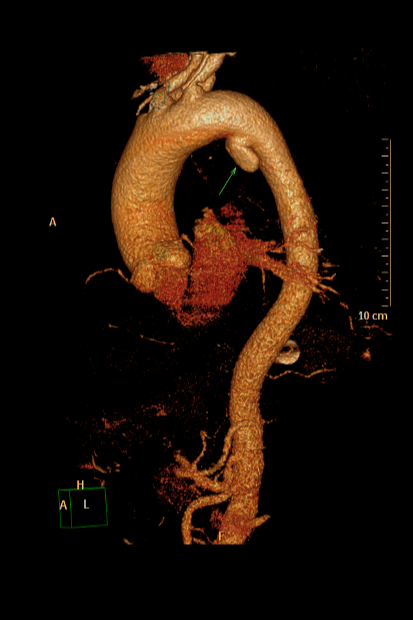

▲ 实例:主动脉瘤合并夹层腔内治疗+弓上三分支腔内重建(血管外科王兵教授团队)